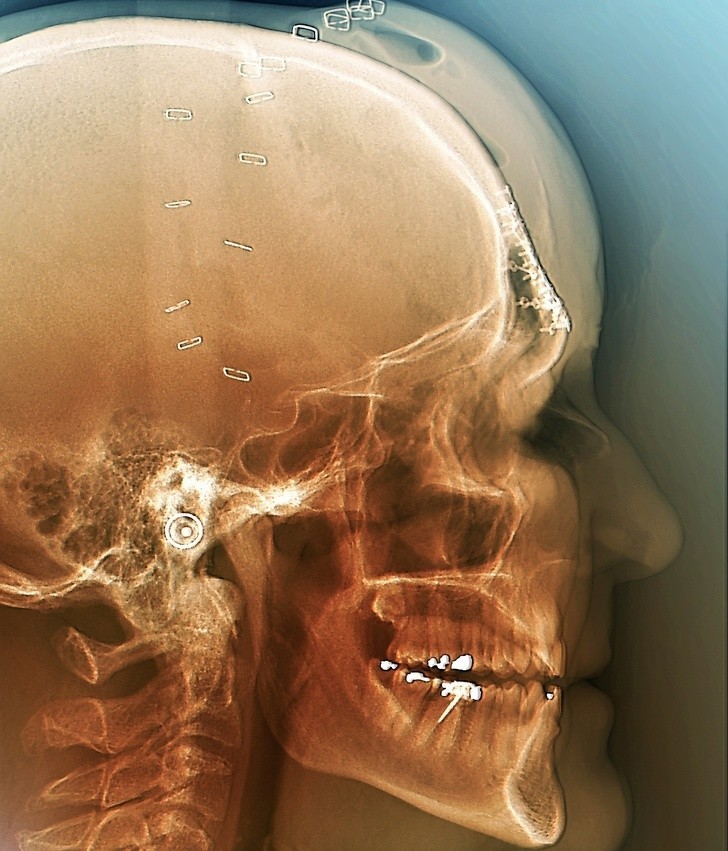

15. Zdjęcie wykonane po operacji mającej na celu zrekonstruowanie czaszki ofiary wypadku samochodowego

15. Zdjęcie wykonane po operacji mającej na celu zrekonstruowanie czaszki ofiary wypadku samochodowego © Zephyr/ SPL / mediadrumworld.com/EAST NEWS